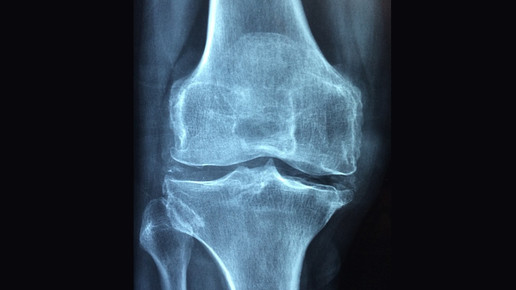

Die Zulassung erfolgte auf Basis einer Hauptstudie mit 52 Kindern im Alter zwischen fünf und zwölf Jahren. Die Probanden wurde alle zwei oder alle vier Wochen mit Crysvita behandelt. Hauptindikator der Wirksamkeit war die Senkung des Schweregrades der Rachitis in Handgelenk und Knie.